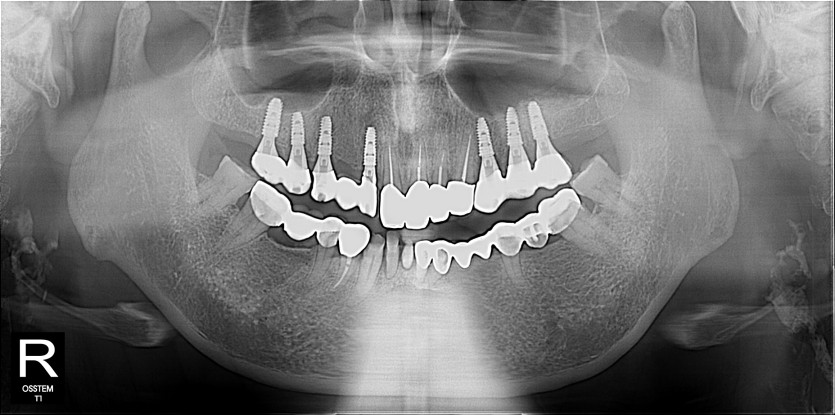

임플란트 사례